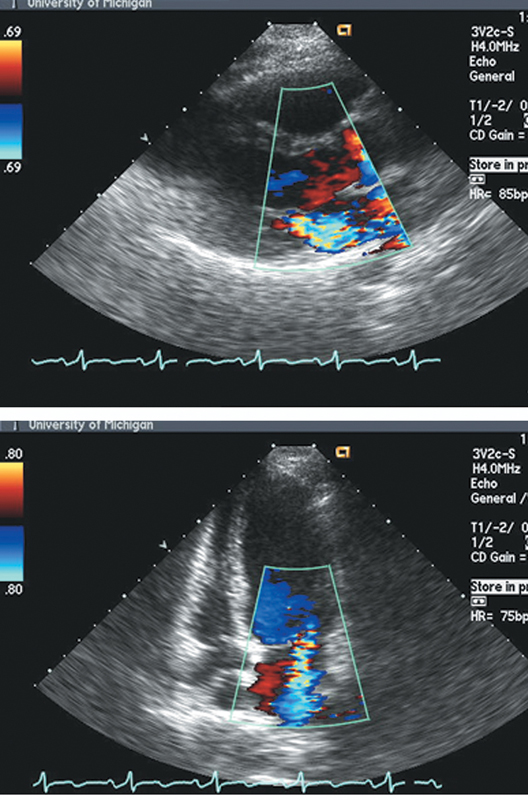

فحوصات تشخيصية لبعض امراض القلب والشرايين التاجية